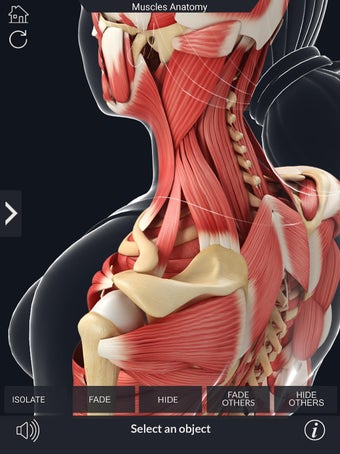

Den mest omfattande mobilappen som finns i världen för att studera muskelanatomi, som låter dig rotera 360°, zooma och flytta kameran runt en mycket realistisk 3D-modell.

Det finns många verktyg tillgängliga för varje muskel, inklusive:

- Rotera 360°.

- Flytta kameran runt modellen.